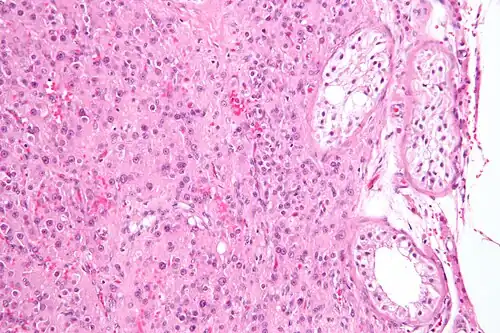

-

Micrograph of a Leydig cell tumour -

Micrograph of a Leydig cell tumour